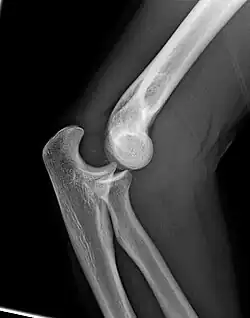

Left: Lateral X ray of a dislocated right elbow

Right: AP X ray of a dislocated right elbow

Dislocation

Elbow dislocations constitute 10% to 25% of all injuries to the elbow. The elbow is one of the most commonly dislocated joints in the body, with an average annual incidence of acute dislocation of 6 per 100,000 persons.[30] Among injuries to the upper extremity, dislocation of the elbow is second only to a dislocated shoulder. A full dislocation of the elbow will require expert medical attention to re-align, and recovery can take approximately 6 weeks.